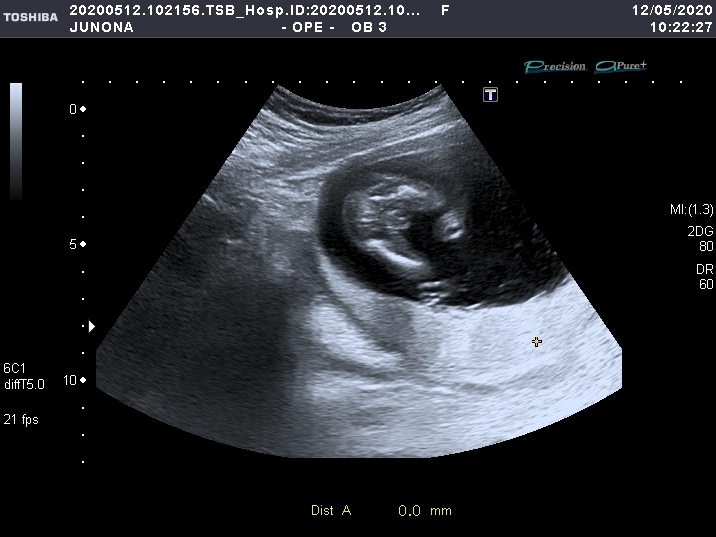

УЗИ, КТГ, доплерНу что, девочки) сходила сегодня на УЗИ) кружок уже закрасила🔘. У нас будет МАЛЬЧИК) Я плакала. Мужу и родным буду сообщать в интересной форме-чуть позже)

Вот он наш мальчишка 👇